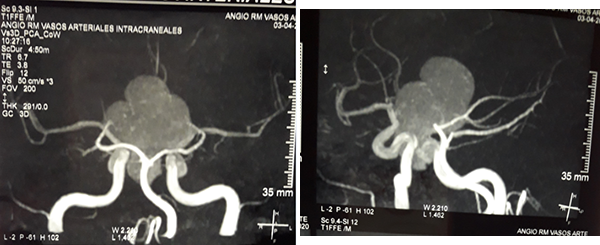

En RM de cerebro se observa lesión espacio ocupante selar-supraselar con aspecto multilobulado que invade cisterna interpeduncular y desplaza estructuras del tercer ventrículo. La misma es hiperintensa espontáneamente en T1 con captación heterogénea de contraste, hiperintensa en T2 (Figura 1). En secuencia de angioresonancia se observa su relación medial respecto a arterias carótidas no comprometiendo las mismas (Figura 2). A partir de éstas imágenes obtenidas en resonador 3 Tesla, en el Departamento de Innovación Tecnológica del Instituto Cardiológico de la Ciudad de Corrientes se realizó un proceso de segmentación de las distintas partes de interés (tumor, arterias, nervios ópticos y globos oculares). Para esto se utilizó el software “Open Source 3D Slicer (versión 4.11)” (Figura 3). Una vez segmentadas las regiones de interés, se realizó, mediante una impresora 3D “MAX” de la empresa Creatbot, un modelo 3D cuyos materiales consistieron en poliácido láctico (PLA) y poliuretano termoplástico (Figuras 4 y 5). Con el mismo, se realizó la planificación del abordaje quirúrgico.

Figura 2: RM en secuencia de angioresonancia a) proyección coronal posterior, observándose arterias cerebrales posteriores circunscribiendo la lesión b) proyección oblicua izquierda y su relación con arterias carótidas y ramas de bifurcación.